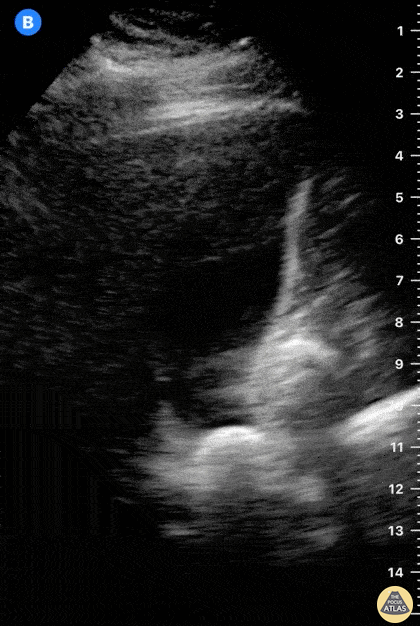

It’s fundamental to study the gallbladder in its whole extension. In this image, there is an impacted stone at the neck. Dr. Felipe Urriola P. www.thepocus.com